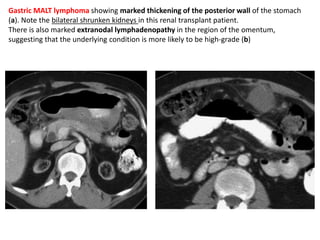

and follow-up examinations with a barium

meal (b) and ultrasound (c)

revealed narrowing of the lumen, typical

irregular folds, and a thickened gastric wall

Linitis plastica

• descriptive term for a tumour of the stomach,

usually a carcinoma, which is diffusely

infiltrating with considerable fibrosis.